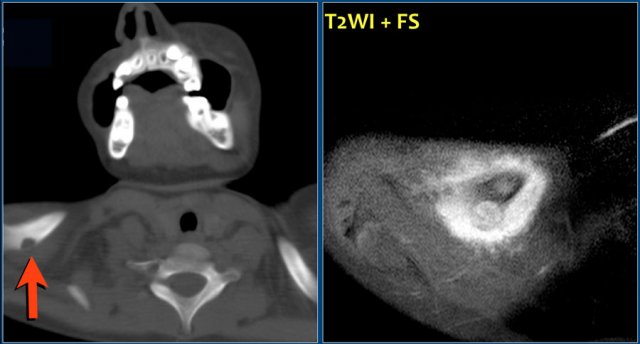

On the left a typical location for an ABC in the posterior elements of the spine.

Notice the well-defined osteolytic presentation with multiple fluid-fluid levels on MR with the patient in supine position.

The differential diagnosis based on the CT is:

ABC, Osteoblastoma and Tuberculosis (1).